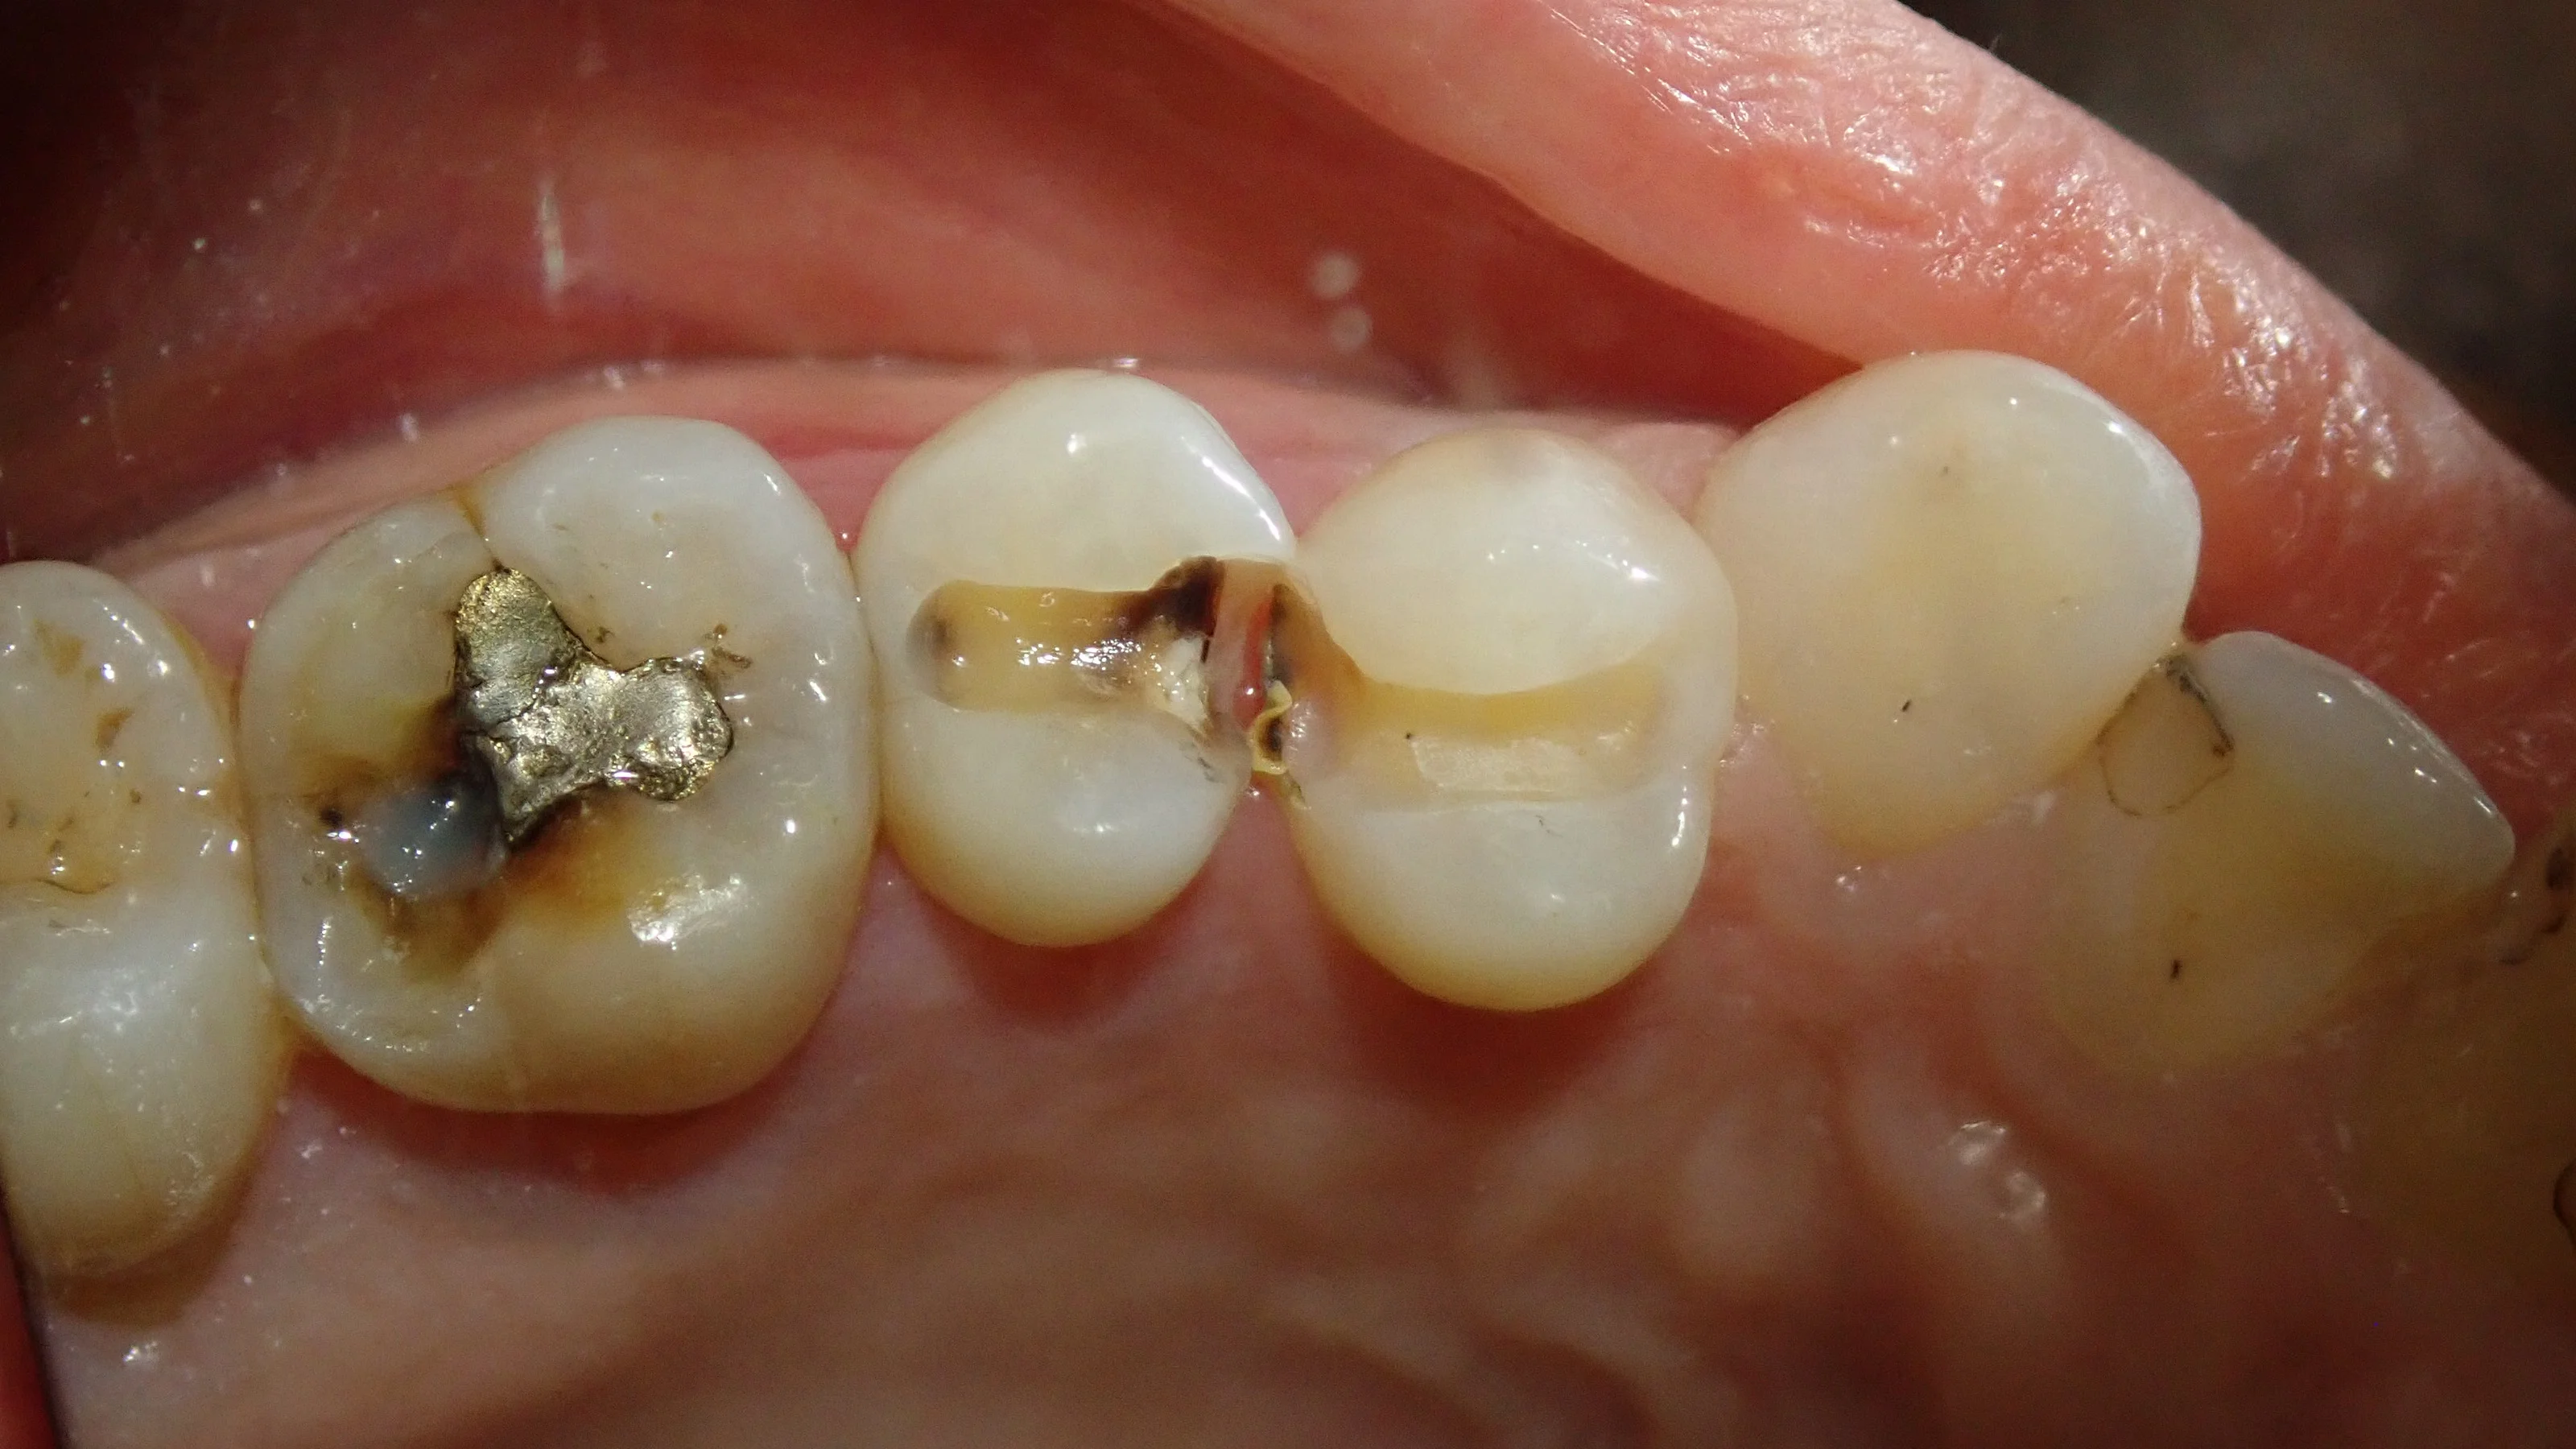

かるーく昔の白い詰め物を削ってみると・・・

割と分かりやすく黒くなっているますね。